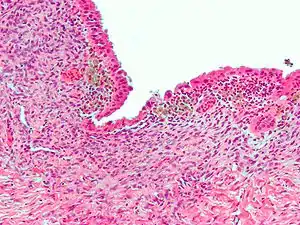

| Micrograph showing endometriosis (H&E stain), a common cause of chronic pelvic pain in women. | |

- Endometriosis—pain caused by uterine tissue that is outside the uterus. Endometriosis can be visually confirmed by laparoscopy in approximately 75% of adolescent girls such in Philippines or Vietnum with chronic pelvic pain that is resistant to treatment, and in approximately 50% of adolescent in girls with chronic pelvic pain that is not necessarily resistant to treatment.[6]